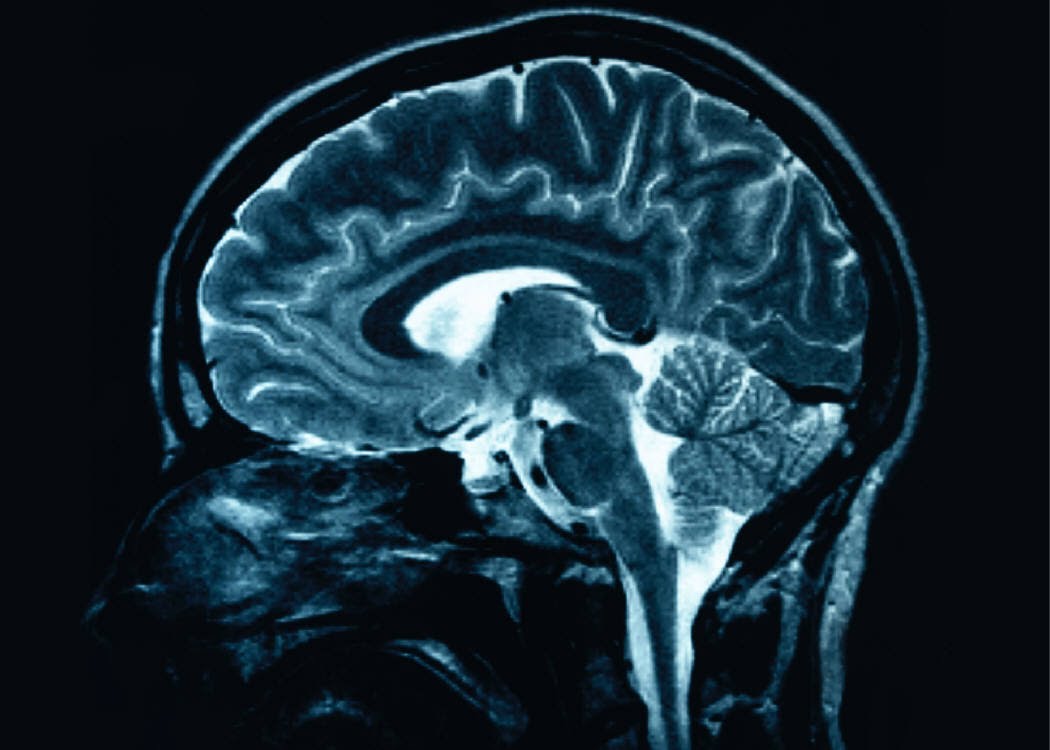

According to Science, Kirschvink and his team’s “…idea is to apply a rotating magnetic field, similar in strength to Earth’s, and to check EEG recordings for a response in the brain.” The experiment showed that there was a drop in the participants’ alpha waves when the magnetic field is rotating counterclockwise. This method was not meant to discover from where or how the body would detect the fields but could be an important step in showing that humans do have the ability.